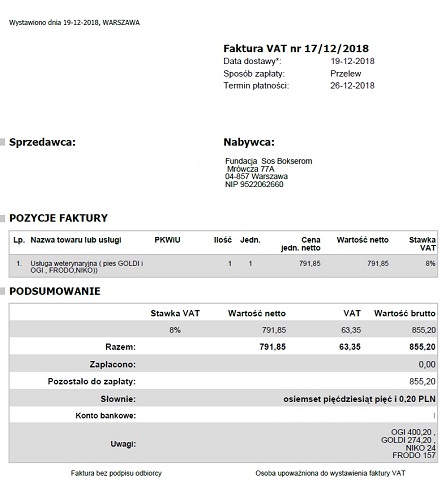

Wizyta Goldiego u kardiologa w 11/2018 to koszt: 120 zł, fvat numer 6/11/2018 oraz 145 zł, fvat numer 14/11/2018.

Leki dla Goldiego to koszt: 274, 20 zł, fvat numer 17/12/2018.

14-letni Goldi czuje się dobrze, dostaje regularnie Karsivan, Theovent i suplementy na stawy. Niedługo czeka go wizyta kontrolna u kardiologa. W listopadzie 2018 po wizycie u kardiologa stwierdzono: Wykonano mu badanie echokardiograficzne serca, które wykazało widoczną zmianę rozrostową przylegającą do łuku aorty i lewego przedsionka.

Wizyta Goldiego u kardiologa w 11/2018 to koszt: 120 zł, fvat numer 6/11/2018 oraz 145 zł, fvat numer 14/11/2018.

Leki dla Goldiego to koszt: 274, 20 zł, fvat numer 17/12/2018.